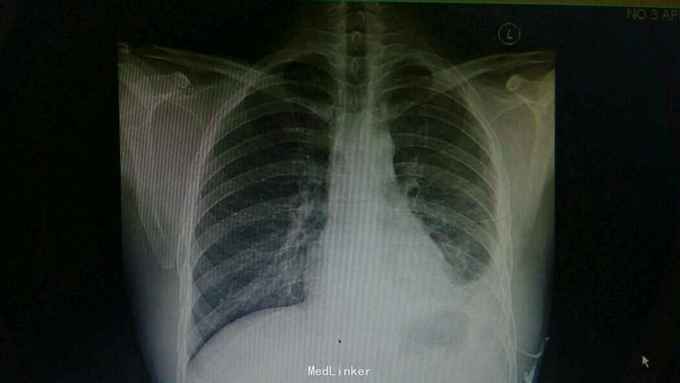

查体:神情,左侧呼吸运动减弱,叩诊浊音,左肺呼吸音低,右侧呼吸性正常。 辅查:胸部CT:左侧大量胸腔积液,左肺受压实变。复查胸片:左侧胸腔积液减前好转。胸水提示渗出性胸腔积液,淋巴细胞为主。T-SPOT:A:64个,B:42个。

诊断:结核性胸膜炎。 治疗:入院结合予以抗结核治疗,胸腔穿刺引流术。